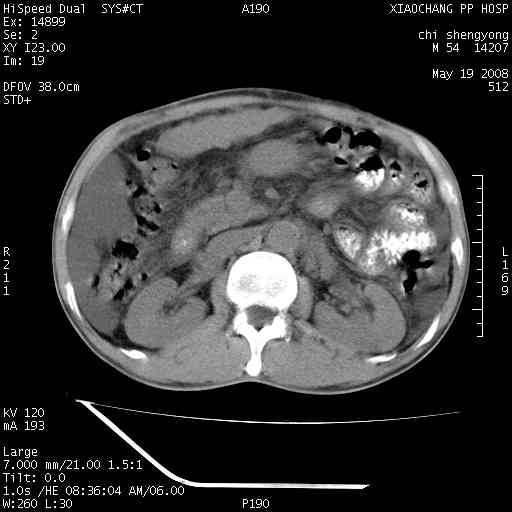

以下是引用zjzjr在2008-5-21 10:52:00的发言:[br]肝左叶巨块型肝癌伴门静脉左支瘤栓形成.肝硬化、腹水,胃底静脉曲张,脾术后改变。

以下是引用随光逐影在2008-5-21 16:20:00的发言:[br]1)肝左叶肝癌伴门静脉左支瘤栓形成,腹膜后淋巴结转移。2)肝硬化、腹水、胃底静脉曲张。3)胆囊炎。4)脾脏缺如,为切除术后所致。